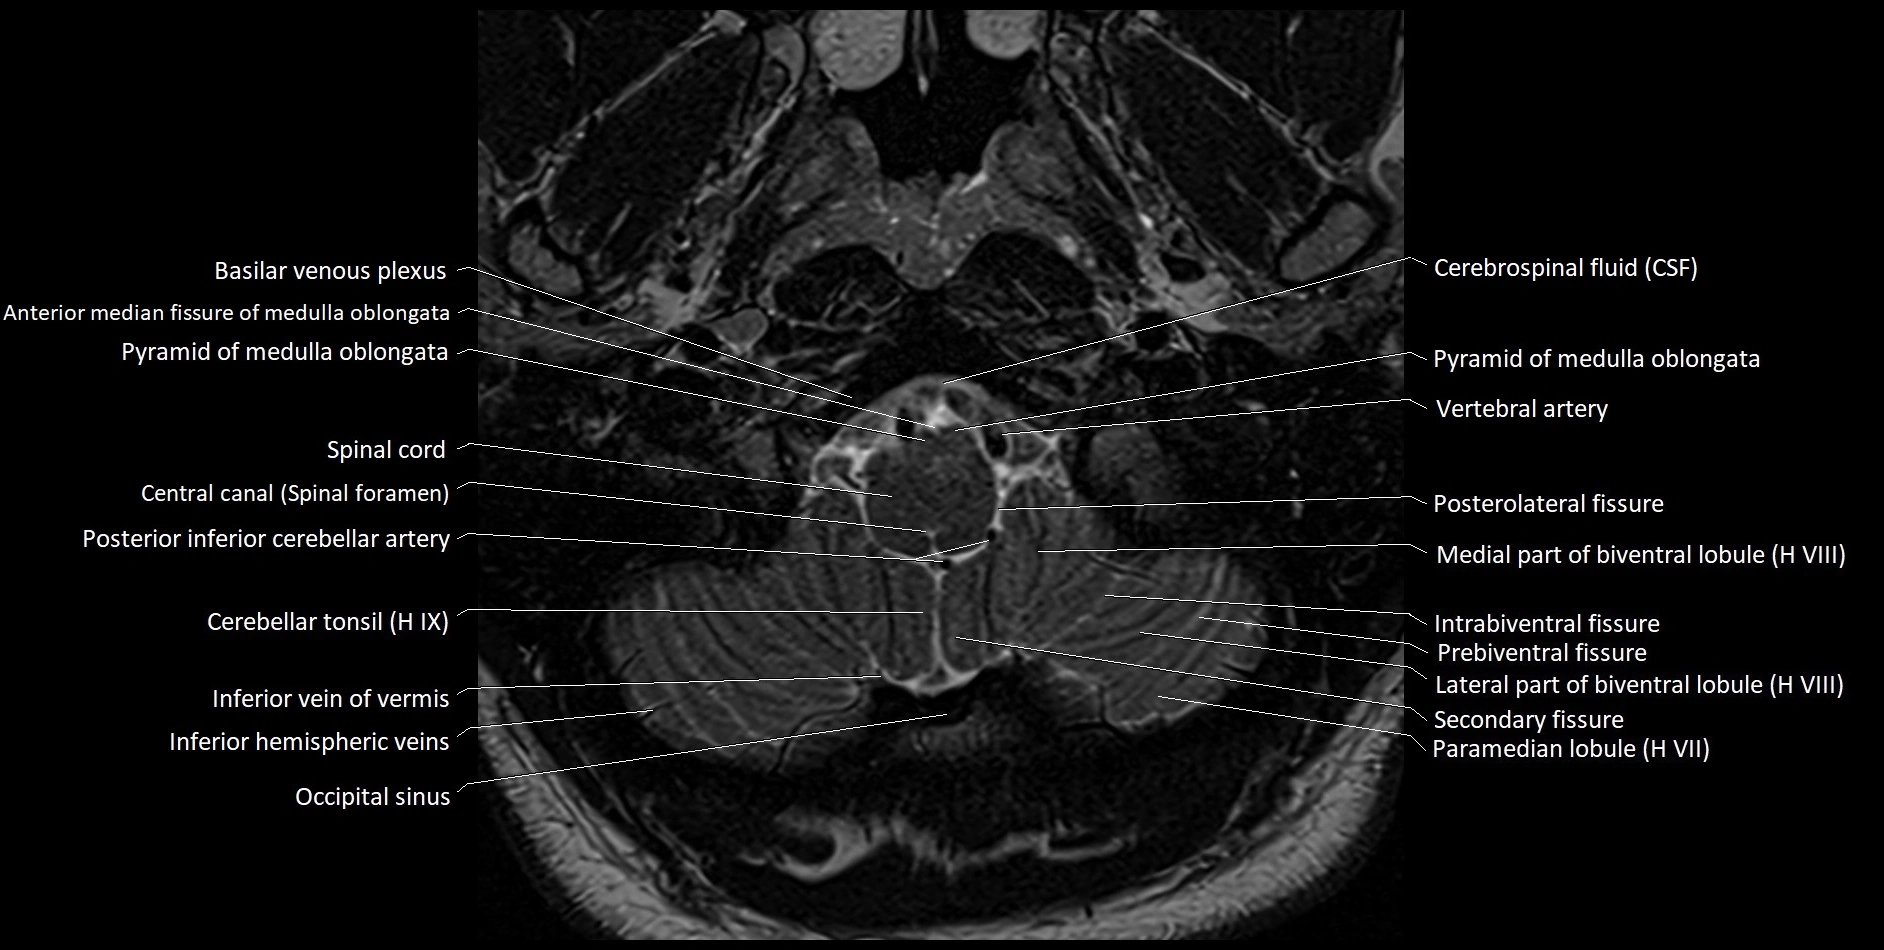

Experience the next generation of cross-sectional anatomy with our advanced 3T MRI, enhanced by AI-powered Deep Resolve reconstruction. Our ultra-high-resolution imaging (0.3–0.7 mm in-plane resolution) combined with ultra-small field-of-view techniques reveals fine anatomical detail with exceptional clarity, redefining anatomical visualization and education.

Explore an advanced library of ultra-high-resolution MRI anatomy, developed from hundreds of repeated scans of volunteers using cutting-edge 3T scanners, dedicated coils, and AI-powered enhancement. These images capture real anatomical detail, revealing even the smallest microstructures while preserving the authenticity of true clinical imaging without over-reliance on virtual labeling.

Learn MRI anatomy like never before—49 body parts, 144 planes

Crystal-clear, high-res images for effective large-screen teaching

All our cross-sectional images are meticulously hand-labeled by professionals with over 20 years of experience in cross-sectional imaging. This is the result of over six years of dedicated work, precision, and passion. Every image is individually checked and verified by senior consultant radiologists from major London NHS trusts, each with relevant subspecialty expertise—ensuring the highest level of accuracy and clinical relevance.